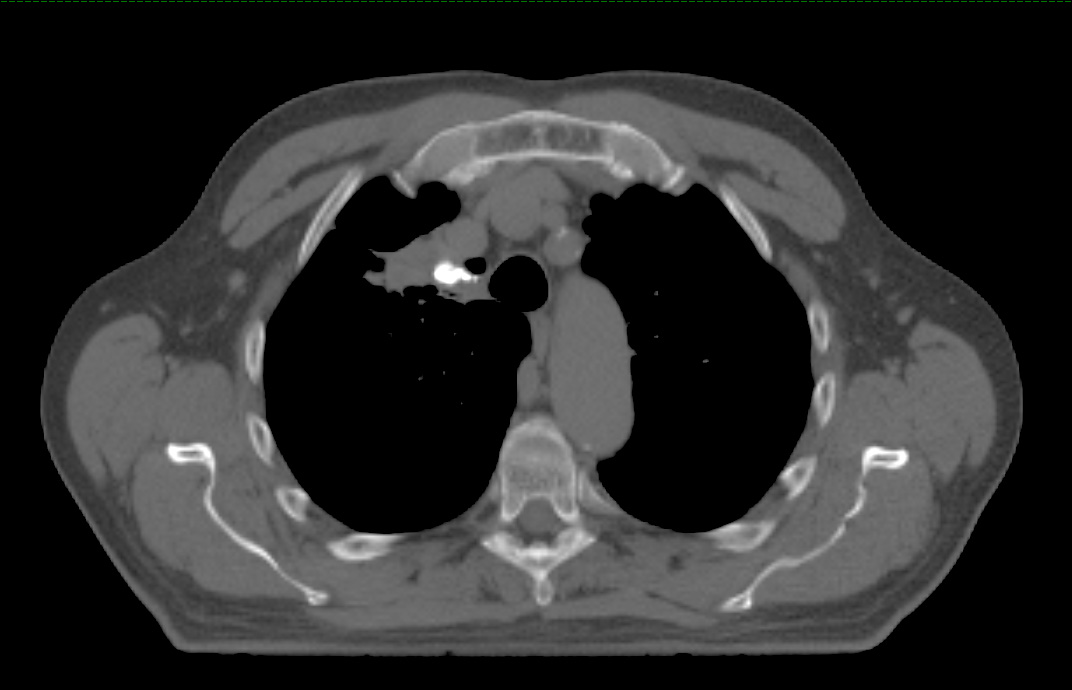

BioXmark® (1mL) is indicated for use to radiographically mark soft tissue in or adjacent to malignant tissue in the thoracic region during a surgical procedure for at least two months after placement. BioXmark® is injected via very thin needles (endoscopically or percutaneously) and provides visibility of the target throughout the treatment. It is biodegradable and is completely resorbed within a few years.

BioXmark® is visible on x-ray, CT, CBCT, fluoroscopy, MRI and ultrasonography enabling multi-modality image-guided planning and treatment, which is becoming the standard treatment approach in radiotherapy in hospitals across Europe. Compared to conventional metal based soft tissue markers, BioXmark® creates limited artefacts in CT and MRI and induces minimal dose perturbation in proton therapy. Moreover, BioXmark® has no sharp edges, which tend to cause migration of conventional metal based markers in patients.

"We have tested BioXmark® in patients with lung cancer and found that it is easy to work with and clearly visible. Markers were injected in tumour tissue, lymph nodes and lung tissue and we observed no migration from the planning CT to end of treatment ,” said Lena Specht, MD, PhD, Professor of Oncology, Dept. of Oncology, Rigshospitalet, Copenhagen University Hospital, Denmark. “ We have also tested BioXmark® in patients with oesophageal cancer and saw no migration between planning CT to end of treatment, and again, BioXmark® was well tolerated."

BioXmark® is the first and only injectable liquid tissue marker which increases viscosity after injection, thereby forming a three dimensional gel-like marker with sufficient contrast for 2D x-ray visualization use. It is easy to inject and visible in all commonly used image modalities. Due to its high radiopacity only a small marker volume is required for sufficient visualization. Since BioXmark® can be injected through thin needles the risk for pneumothorax in lung cancer is reduced.